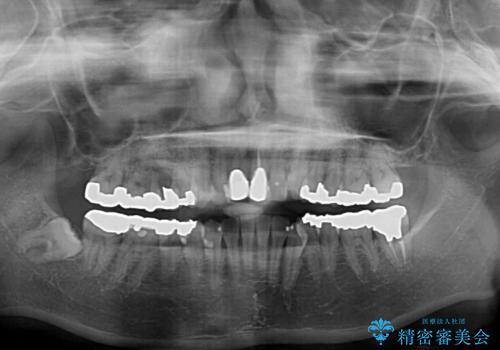

- 前歯のデコボコとセラミッククラウン周りの黒い縁を気にして来院された患者様です。

前歯の黒い縁は、矯正治療後にオールセラミッククラウンにて改善することとしましたが、いち早く目立たなくしたいとのことで、事前に矯正治療用仮歯に置き換えてから矯正治療を開始しました。

口元が前方に突出することもなく、綺麗に仕上げることができました。